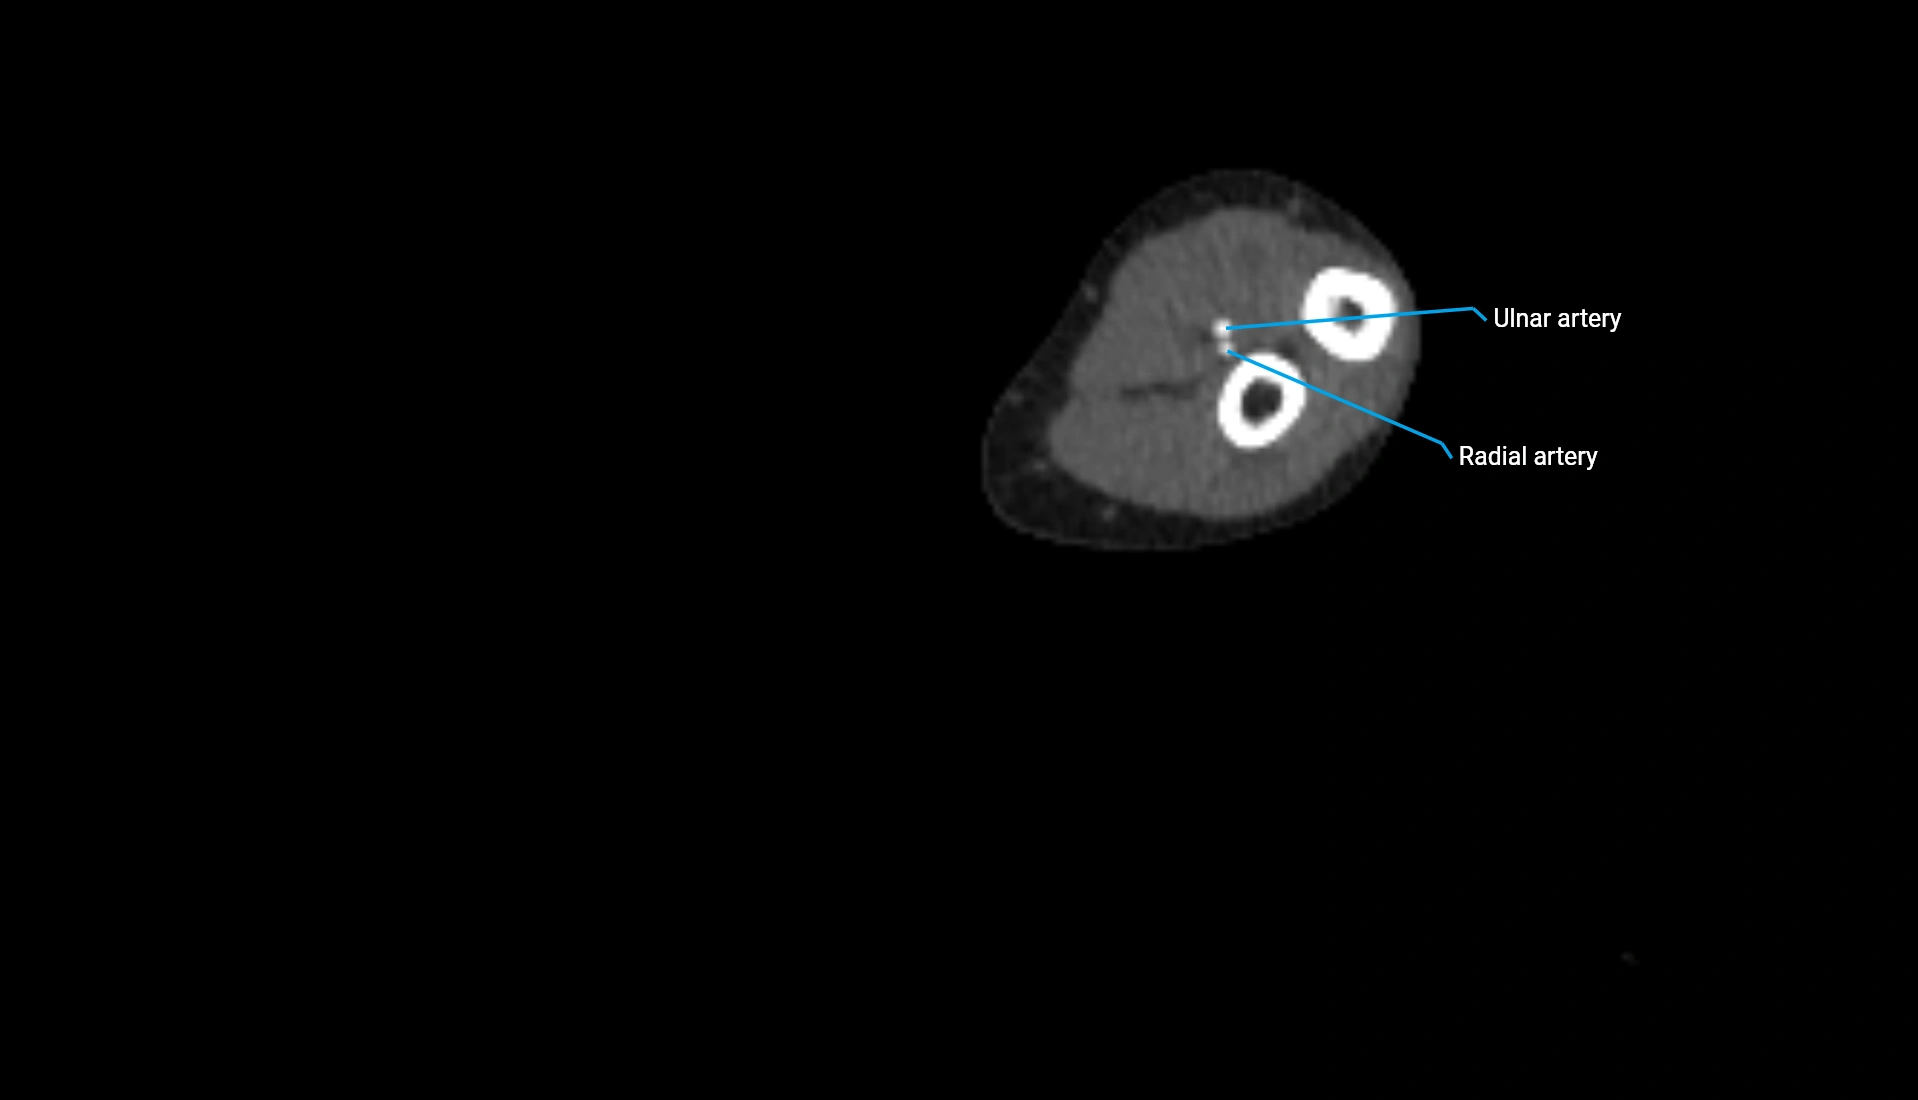

CT Appearance

Non-Contrast CT:

• Cortex: High-density, sharply defined

• Subchondral bone: Dense cancellous matrix

• Articular surface: Smooth concave contour articulating with the capitellum

• Excellent for evaluating bone integrity, alignment, and subtle fractures